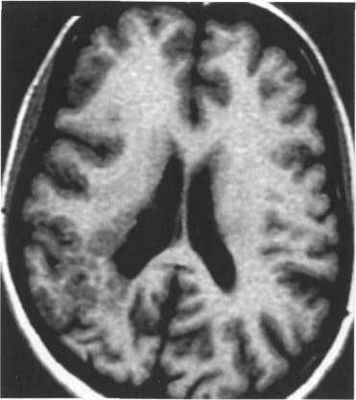

Лентовидная гетеротопия, или синдром двойной коры, проявляется четко очерченным лентовидным слоем нейронов, отделенным от коры полосой белого вещества. Диагностировать данную патологию можно только по данным МРТ. При этом на изображениях выявляется ровная, четко очерченная полоса серого вещества, расположенная параллельно боковому желудочку и отделенная от коры и стенки желудочка слоем серого вещества. Кора мозга может быть неизмененной либо может быть изменена от умеренно выраженной пахигирии до полной агирии (рис. 3.21). В белом веществе на Т2-ВИ могут определяться очаги гиперинтенсивного сигнала. Лентовидную гетеротопию достаточно сложно дифференцировать с лиссэнцефалией: они, вероятно, представляют собой различные степени одного общего процесса нарушения миграции нейронов. В отличие от лиссэнцефалии, при лентовидной гетеротопии изменения коры выражены меньше.

Рис. 3.21. Лентовидная гетеротопия. МРТ.

а - IR ИП, аксиальная плоскость; б - Т2-ВИ, аксиальная плоскость.

Полоса гетеротопированного серого вещества отделена

слоем белого вещества от коры и желудочков мозга.